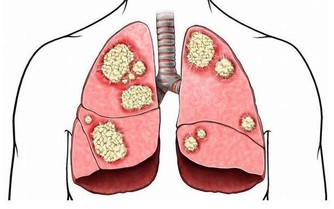

有研究表明,使用不潔的洗浴設施,有可能感染熱浴盆肺、綠膿桿菌所致毛囊炎、軍團病等疾病。